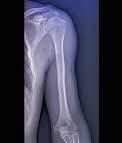

O diagnóstico nem sempre é simples, já que a dor é gradual. “Além da avaliação clínica feita pelo médico, radiografias são fundamentais no diagnóstico, pois mostram a presença de osteófitos (“bicos”), cistos, deformidade articular e pinçamento da articulação (não há mais espaço entre os ossos – o úmero fica “encostado” na glenoide)”, conta Schiefer. Tomografia e ressonância também podem ser utilizadas conforme a necessidade de cada caso.